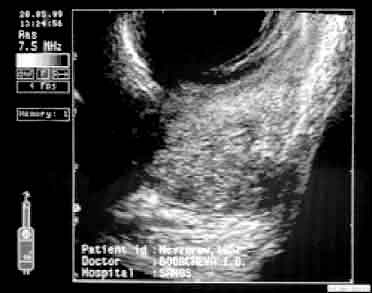

| ТРУЗИ простаты больного М., 1952 г.р. до лечения. Поперечное (а) и продольное (б) сканирование. Снижение эхогенности ткани в области верхушки железы и в виде радиальных полос от вентральной поверхности к центру железы - результат пальцевого массажа. Определяется периуретральный и паравезикальный отек. | |